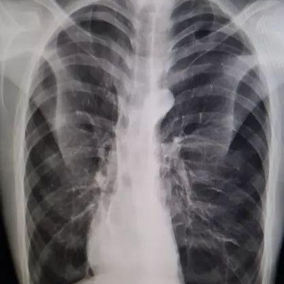

After a preoperative examination, it is observed that the patient's anterior chest wall protruded severely, reaching its peak at the xiphoid process, which presented as a 90-degree angle when viewed from the side. The heart is displaced to the right chest cavity, and the torso is severely deformed, characterized by a broad chest and a noticeably narrowed waist and abdominal area. The narrowing is most pronounced above the pelvis. Moreover, a chest CT scan reveals two large cysts located between the heart and the anterior chest wall in the lower lobe of the left lung, measuring 7x8 cm and 9x10 cm respectively.

We developed and executed a personalized minimally invasive surgical treatment plan for the patient. The Wung procedure and the Wenlin procedure was performed during the operation. First, a 3 cm longitudinal incision was made on the left chest wall to insert a thoracoscope, which was used to explore and remove the cysts on the left lung. Second, another 3 cm incision was made on the right chest wall and two passage tunnels were constructed for the bars between these two incisions. A third tunnel was then constructed near the costal arch, and three pre-shaped bars were inserted into the tunnels to correct the deformity. Lastly, the bars were securely fixed, and the incisions were sutured. The surgery was successfully completed in 2 hours, effectively eliminating the malformation and restoring the chest wall to an almost normal appearance.